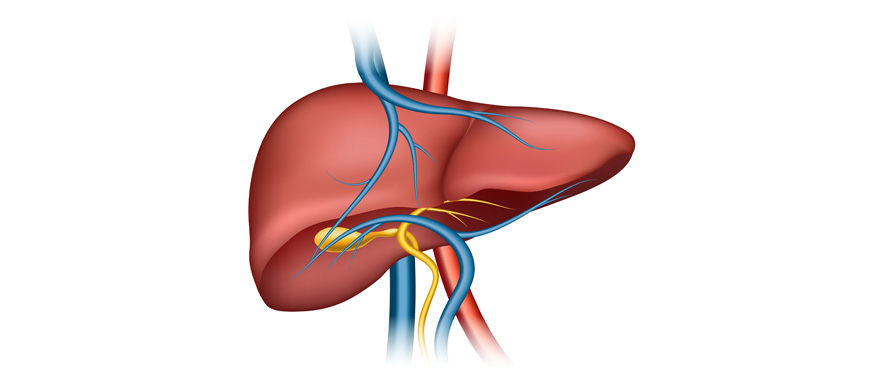

Χειρουργική Ήπατος

Χειρουργική Ήπατος – Αντιμετώπιση Παθήσεων Ήπατος

Το ήπαρ είναι ένα ζωτικό όργανο με κεντρικό ρόλο σε πλήθος λειτουργιών του οργανισμού, όπως ο μεταβολισμός, η αποθήκευση θρεπτικών ουσιών, η αποτοξίνωση του αίματος και η παραγωγή χολής. Παρά την ανατομική και λειτουργική του πολυπλοκότητα, διαθέτει μια μοναδική ικανότητα: την αναγέννηση. Αυτό επιτρέπει στους χειρουργούς να αφαιρούν σημαντικά τμήματα του ήπατος, όταν αυτό απαιτείται, διατηρώντας παράλληλα τη συνολική ηπατική λειτουργία.